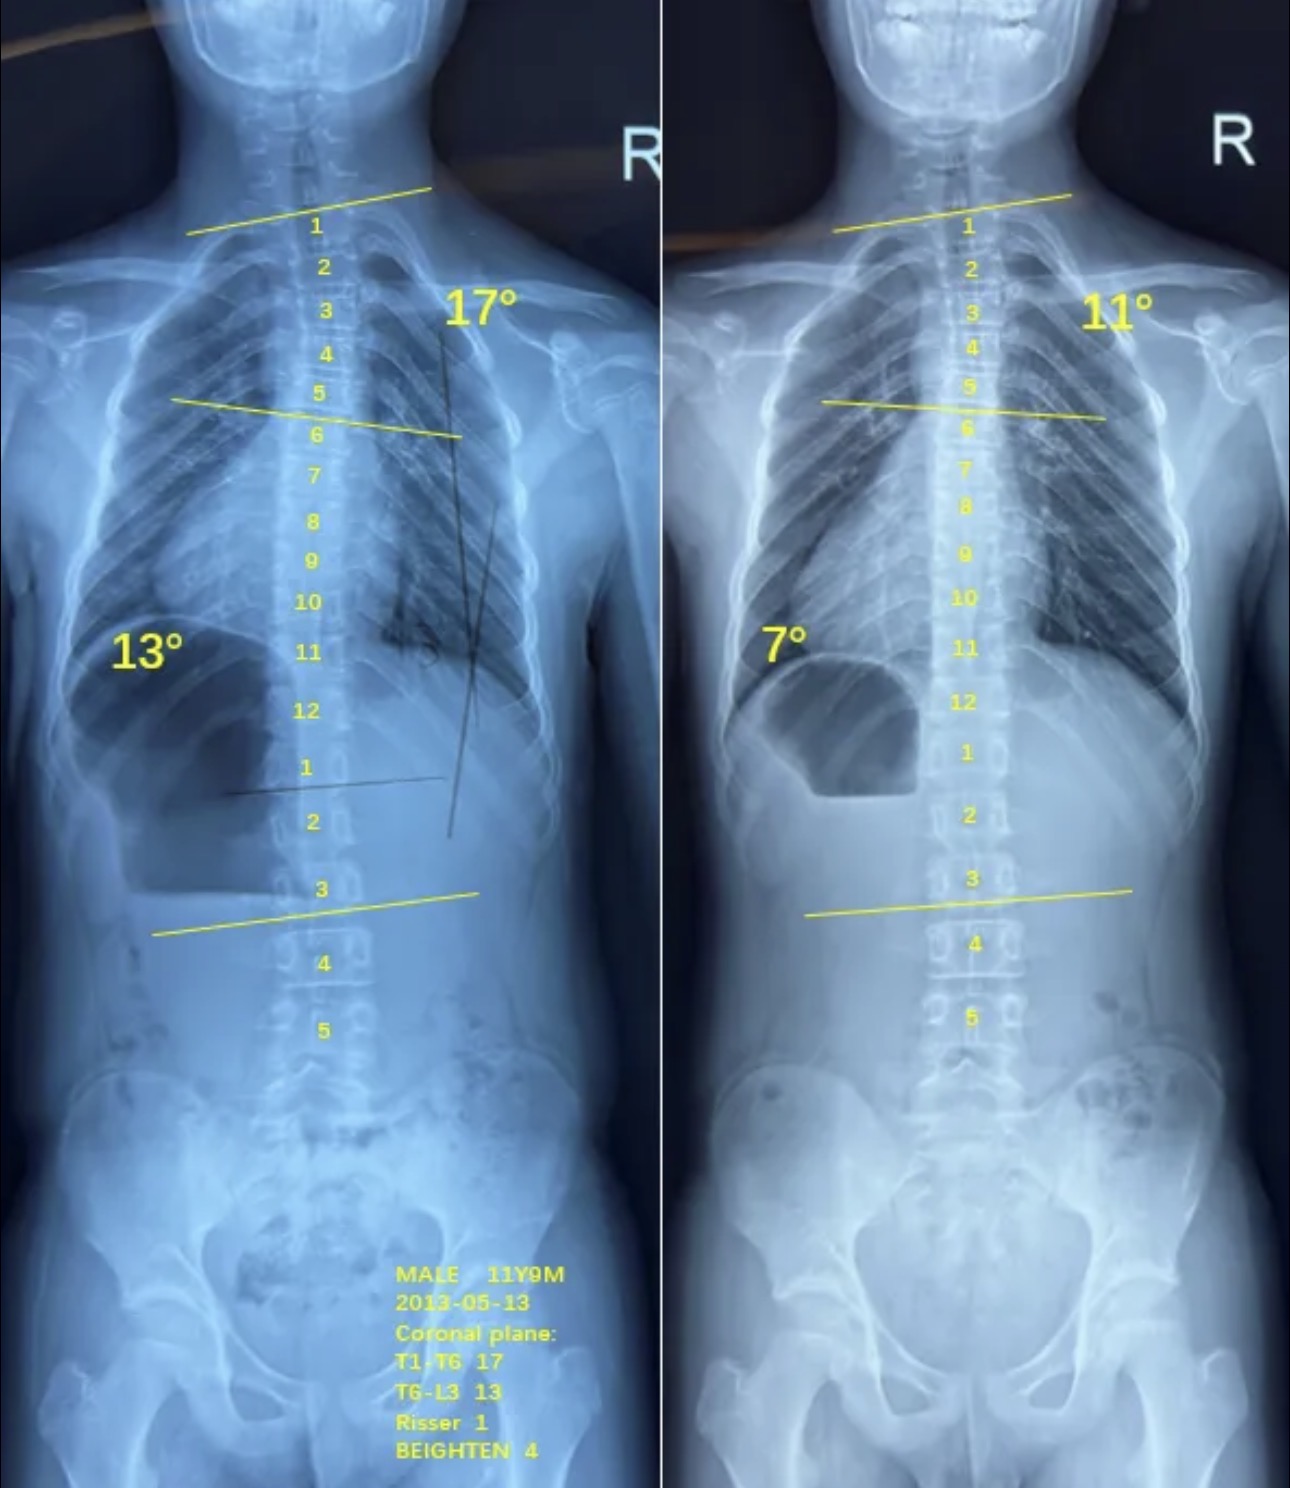

衷德脊柱,我们只关注侧弯保守治疗~

Zhongde Spine, bending no breaking ~